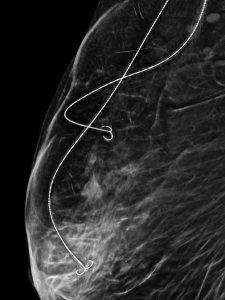

În cadrul SCJU Constanța – Secția Chirurgie 1, sub coordonarea Prof. Univ. Dr. Răzvan Popescu, a fost realizată în premieră o intervenție de conservare a sânului în cazul unei paciente cu trei leziuni maligne, prin tehnica Bracketing cu două harpoane.

-Dr. Alexandru Gavrilă – medic primar radiologie și imagistică medicală, cu competență în senologie